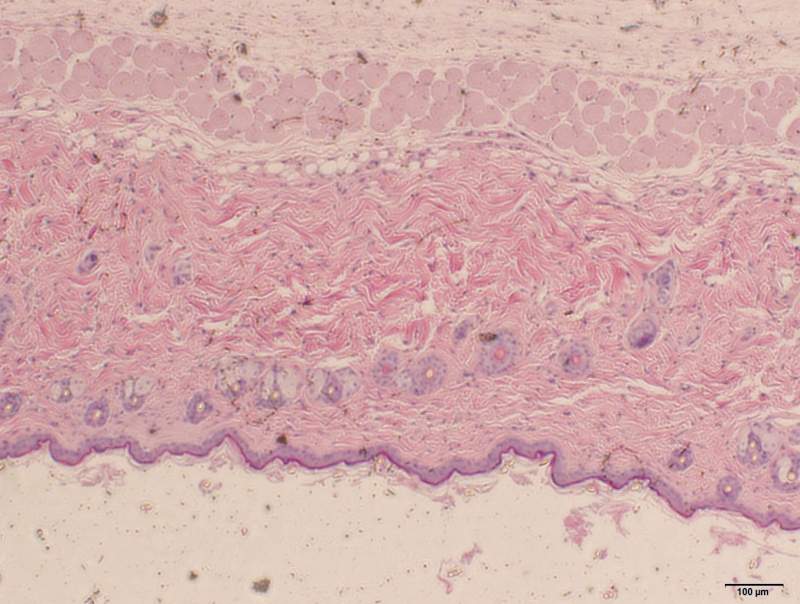

ÎÒÏë²âÁ¿Ð¡ÊóÕæÆ¤²ãºñ¶È£¬²»ÖªµÀÕæÆ¤²ãÊÇ´ÓÄĵ½ÄÄÀï¡£ÇëÔÚÎÒÉÏ´«µÄÕÕÆ¬ÉϱêעСÊ󯤷ôÕæÆ¤²ãÆðʼλÖã¡Ð»Ð»£¡ ʵB4 40.jpg ¿ÕA4 100.jpg |

ÎÒ²»È·¶¨ÊÇ´ÓºìÉ«¿ªÊ¼»¹ÊÇÂÌÉ«¿ªÊ¼£¬²»¹ý°´ÕÕÈËÀàÆ¤·ôµÄ»°£¬ÕæÆ¤²ã´ó²¿·ÖÓ¦¸ÃÊǽºÔµ°°×ÏËά£¬ËùÒÔ¹À¼ÆÊÇ´ÓºìÉ«¿ªÊ¼µÄ¿ÉÄÜÐÔ´ó w132h2020088_1394102873_568.jpg w132h2020088_1394102883_469.jpg |

ÖØÉú²½Ô¶: ½ð±Ò+8, ¡ïÓаïÖú, ÓÐÎÄÏ×ÖÐСÊóÕæÆ¤²ãºñ¶È´ó¸ÅÔÚ300¦Ìm×óÓÒ£¬Ó¦´ðÕß±ê×¢µÄÕæÆ¤²ãºñ¶È²»ÔÚ300΢Ã××óÓÒ¡£²»¹ý»¹ÊÇллÁË£¡ 2014-03-22 20:11:54